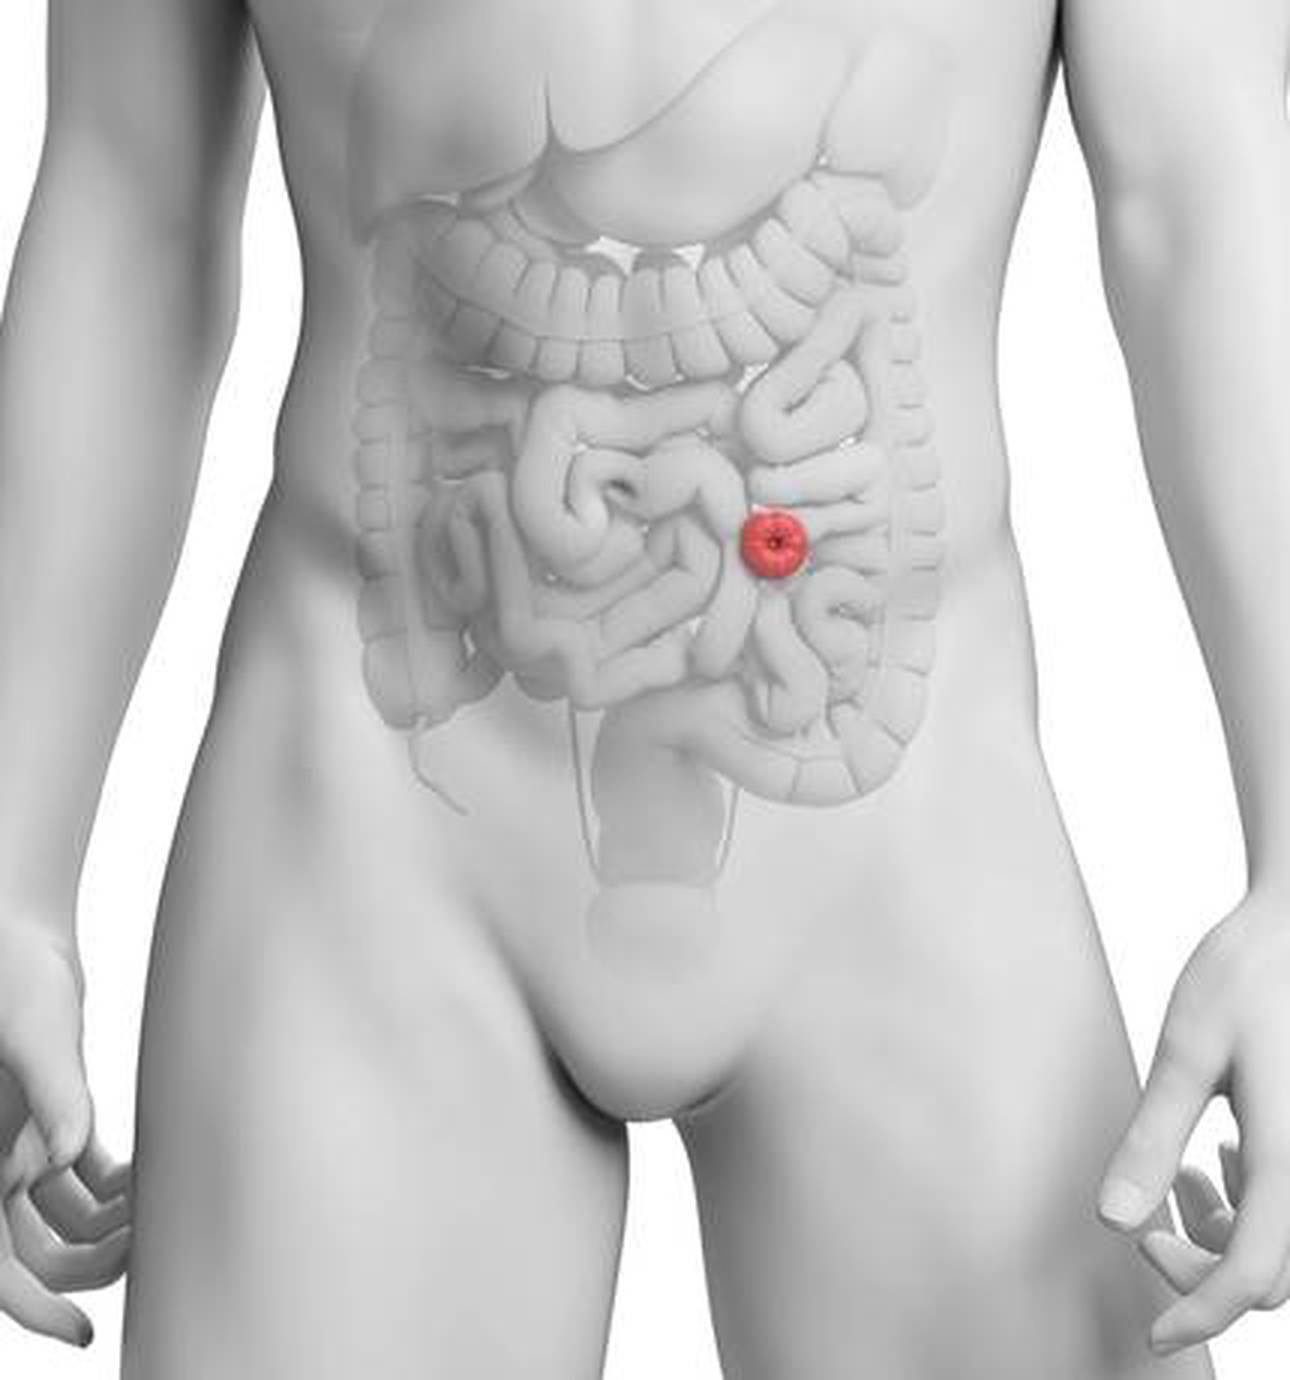

St Mark’s already offers complex treatments for patients with advanced and recurrent bowel cancer and is one of a handful of units across the UK offering complex interventions.

The surgical work at St Mark’s Hospital specialises in advanced techniques for the treatment of both common and unusual problems of the small and large bowel and of the anus.

The inherited intestinal cancer syndromes are more commonly known as polyposis and Lynch Syndrome.